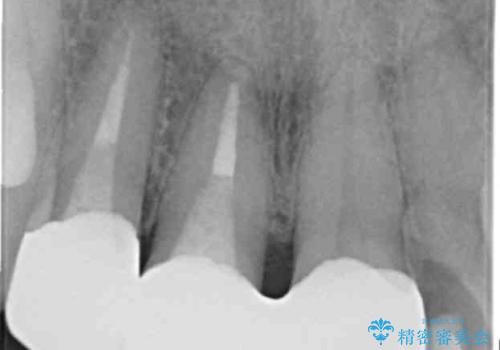

右上の前歯二本、左上の前歯1本をセラミックにし、正中の前歯を2本連結しました。

- 60.5万円(税込み) ジルコニアクラウンスペシャル 14.3万円x3 仮歯 1.1万円x3 右上1、右上2:ファイバーコア 2.2万円x2 右上1: 精密根管治療(リトリートメント) 9.9 万円x1費用は治療当時の料金となります

歯周病や楽器の影響などですき間が生じることはありますが、今回は開いてきた原因はわからないため、連結するか、ナイトガードをはめて歯ぎしりで力がかかりすぎないようにすることが大事になってきます。

- 根管治療により痛みや腫れがひかない事や、術後に痛みや腫れが生じる事、治療によるファイル破折やパーフォレーションなどの偶発症、術後の歯根破折を生じる可能性もあります